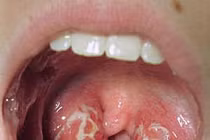

(khoahocdoisong.vn) - Viêm amidan thông thường có thể tự khỏi mà không cần điều trị. Tuy nhiên, không ít trường hợp viêm amidan có thể gây biến chứng nguy hiểm.